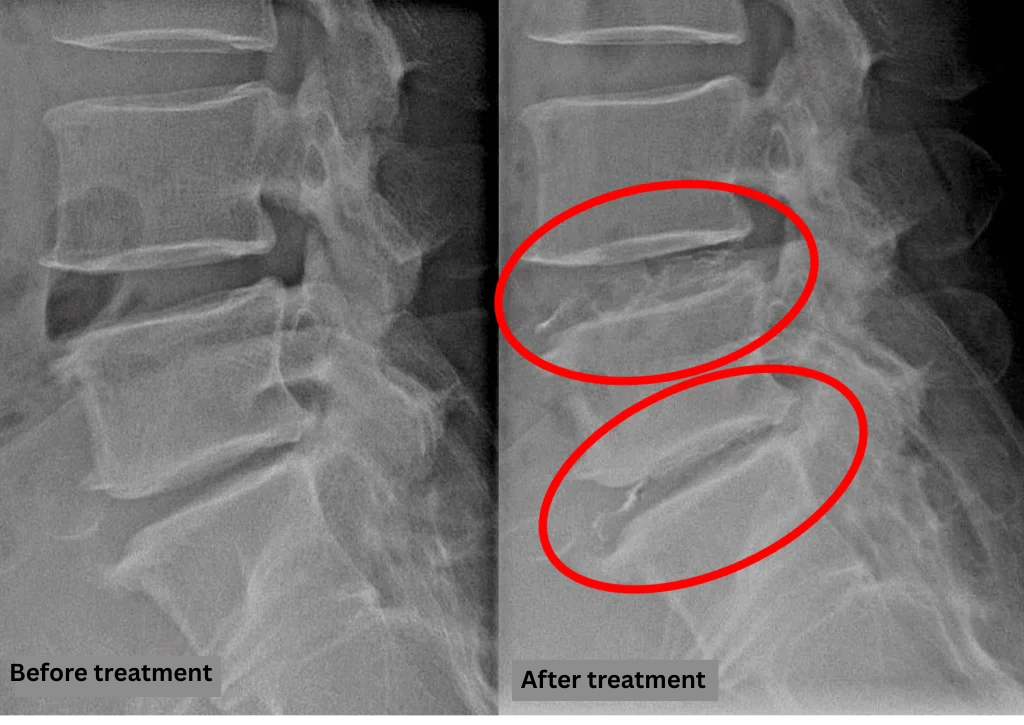

Treatment

After consulting with the patient, the Cellgel Method was performed on L4/5 and 5/s.

The treatment was performed by Dr. Ohara.

The treatment took about 30 minutes.

After resting in the recovery room, the patient was able to walk home unaided.